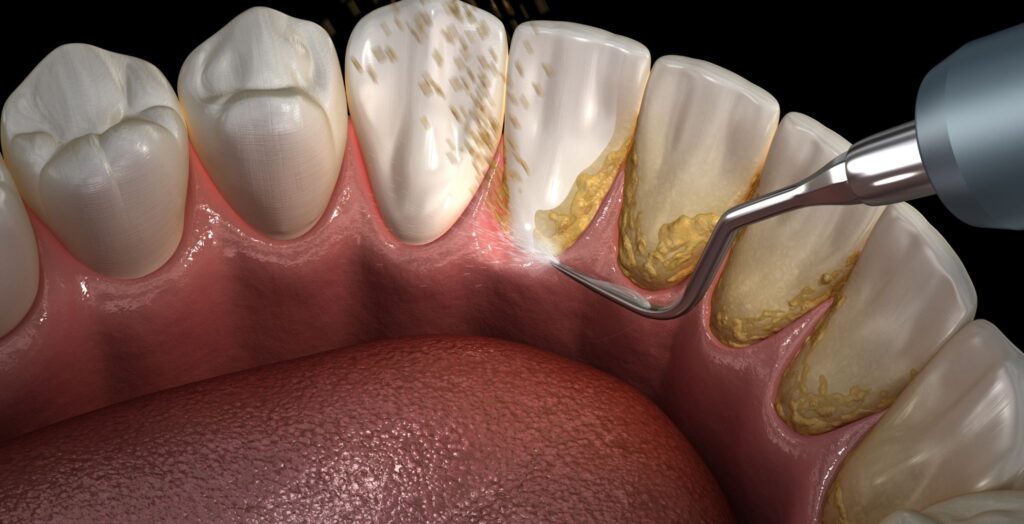

Removing Dental Plaque: Effective Techniques for Healthy Teeth

Think of your teeth like tiny houses in your mouth. Just like houses can get dirty, your teeth can too! But instead of dust, a sticky film called dental plaque builds up on them. This blog will tell you all about this plaque, why it’s important to get rid of it, and how to keep […]